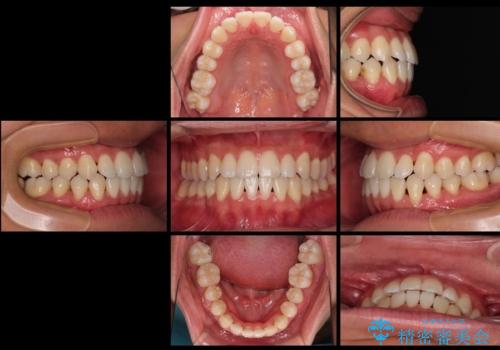

歯列弓の拡大により約1年で矯正治療を終えることができました。

正中も合わせることができ、非常にきれいに仕上がりました。